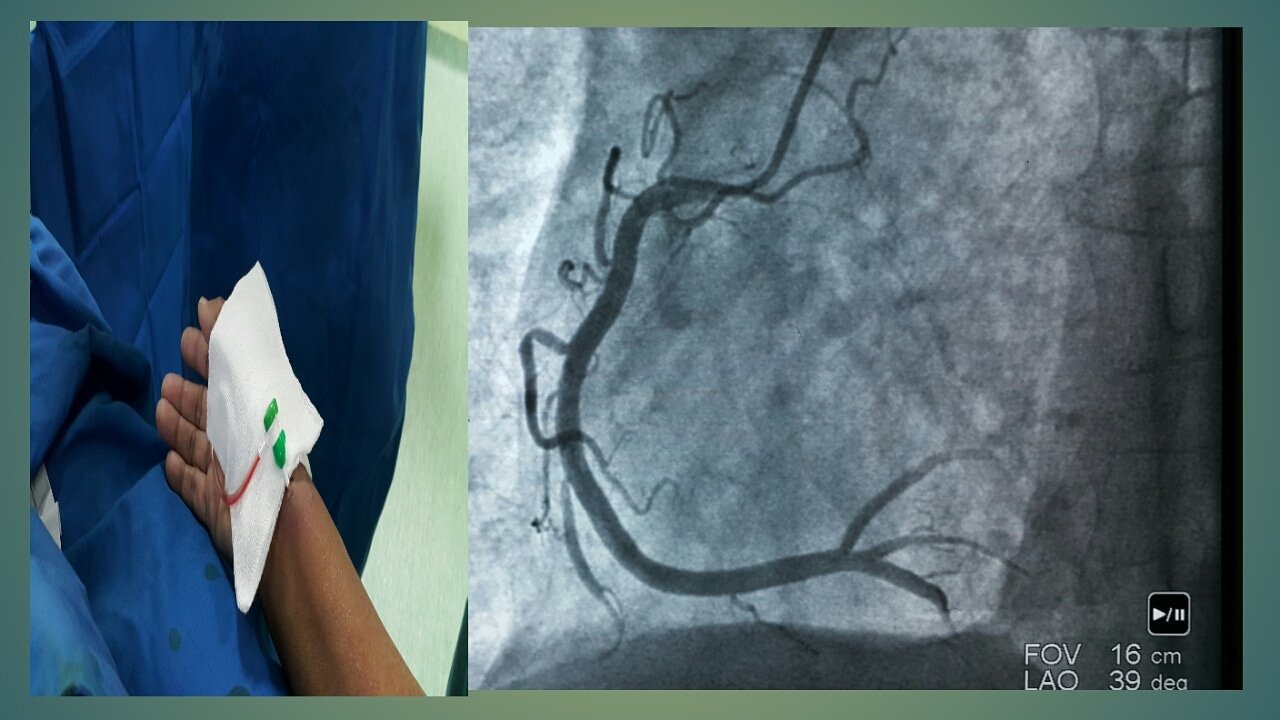

Ангиография при узелковом полиартериите: особенности исследования